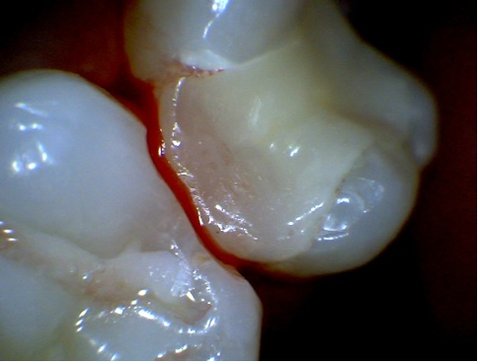

인레이 후 인레이 제거한 모습

인레이 후, 살짝만 건드려도 피가나고 옆치아까지 삭제된 모습